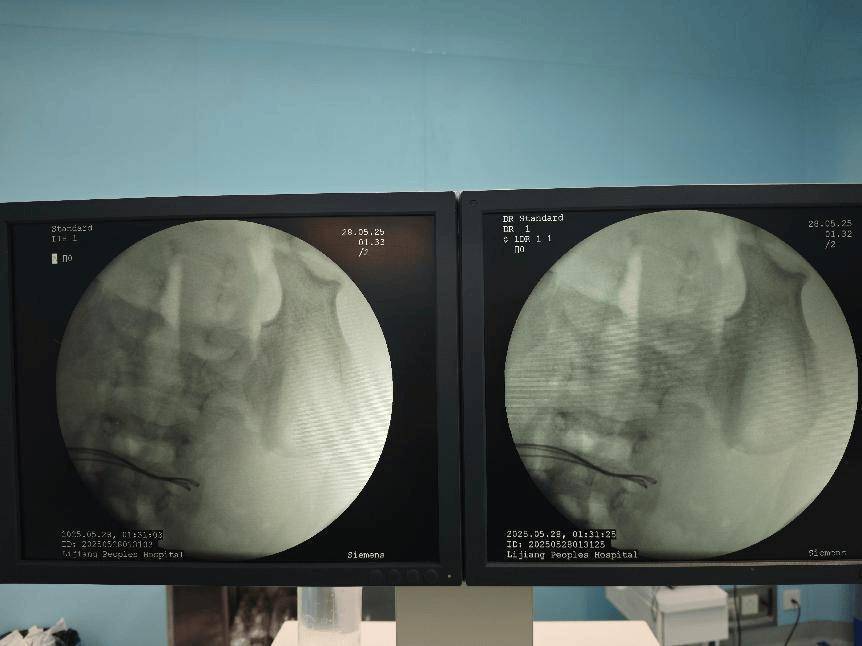

术前腹部DR片

面对如此严重的病情,丽江市人民医院普外一科立即启动了紧急救治程序,组织专家团队进行会诊,并制定出了周密的手术方案。但手术过程中,医疗团队发现了比预想中更为复杂的情况:病人小肠内的异物竟然是被称为无声“肠道杀手”的磁力珠。

术中完善床旁DR见腹腔内已无异物